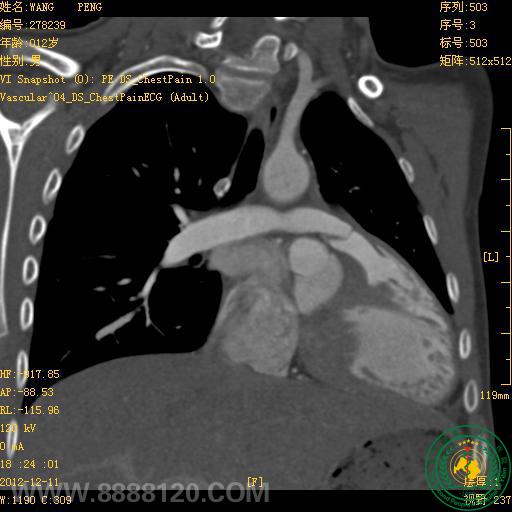

我院炫速双源CT正式投入使用第二周,今天即对1例高心率(114次/分钟)法洛氏五联症合并动脉导管未闭患者作了心脏、冠状动脉、主动脉和肺动脉检查,一次扫描,快速、准确诊断。

1.右心室增大,室间隔干下部缺损,房间隔卵圆孔缺损,主动脉骑跨室间隔,肺动脉主干和右室流出道狭窄,诊断为法洛氏五联症,双侧下肺动脉明显加宽。

2.主动脉弓和肺动脉主干间见通道,诊断为动脉导管未闭。

3.左、右冠状动脉未见异常。